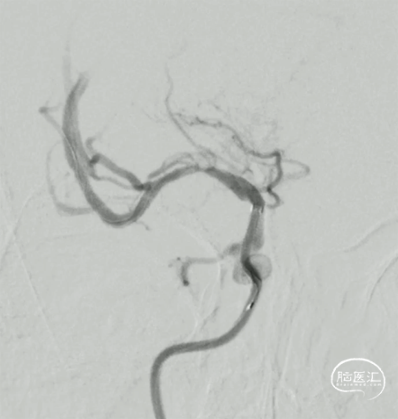

右侧大脑中动脉起始部闭塞,左侧前交通开放,左侧大脑前动脉通过软膜支代偿,大脑后动脉通过软膜支代偿,侧支代偿可,考虑粥样硬化合并急性闭塞的可能。

释放Syphonet®取栓支架 5*35mm,造影显示:支架释放效应可疑阳性。

造影:考虑局部血栓可能。

取栓后造影,M1再通,局部狭窄可能,前向血流延迟。

M1局部狭窄,合并小血栓可能。